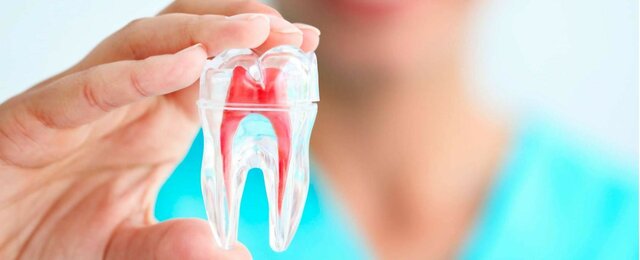

En Estados Unidos, Herbert Shilder introdujo el concepto de limpieza y conformación (cleaning and shaping). La limpieza hace referencia a la eliminación de todos los contenidos del sistema de conductos radiculares. La conformación se refiere a una forma específica de cavidad, realizado con cinco principios o reglas de oro en la especialidad.